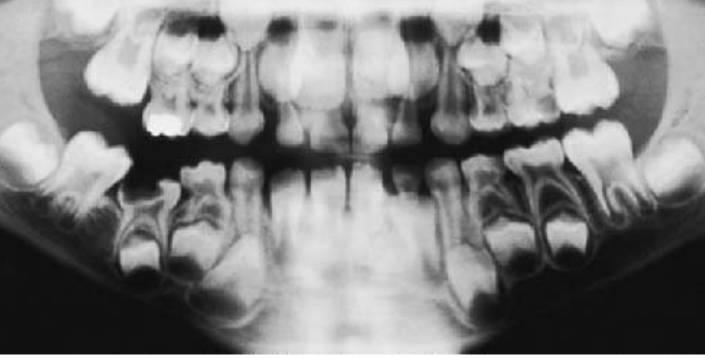

Cuando se pierde de forma prematura un segundo molar temporal debido a caries o a la erupción ectópica del primer molar permanente éste se mesializará, y este hecho se verá más pronunciado en el maxilar, donde se produce un desplazamiento más rápido del molar, provocando una maloclusión de clase II. Cuanto más temprana sea la pérdida del segundo molar temporal y menor sea el desarrollo de la raíz del molar permanente, mayor será la cantidad de desplazamiento mesial total del molar permanente.

Siempre que se produzca la pérdida prematura de un segundo molar temporal, antes o después de la erupción del primer molar permanente, se producirá alguna pérdida de longitud de arcada provocada por el desplazamiento mesial del molar permanente (fig. 11.3).

El mantenimiento del espacio resulta crítico en niños que tienen una longitud de arcada normal y pierden un molar temporal. Cualquier pérdida de espacio en estos niños provocará el apiñamiento de los dientes permanentes.